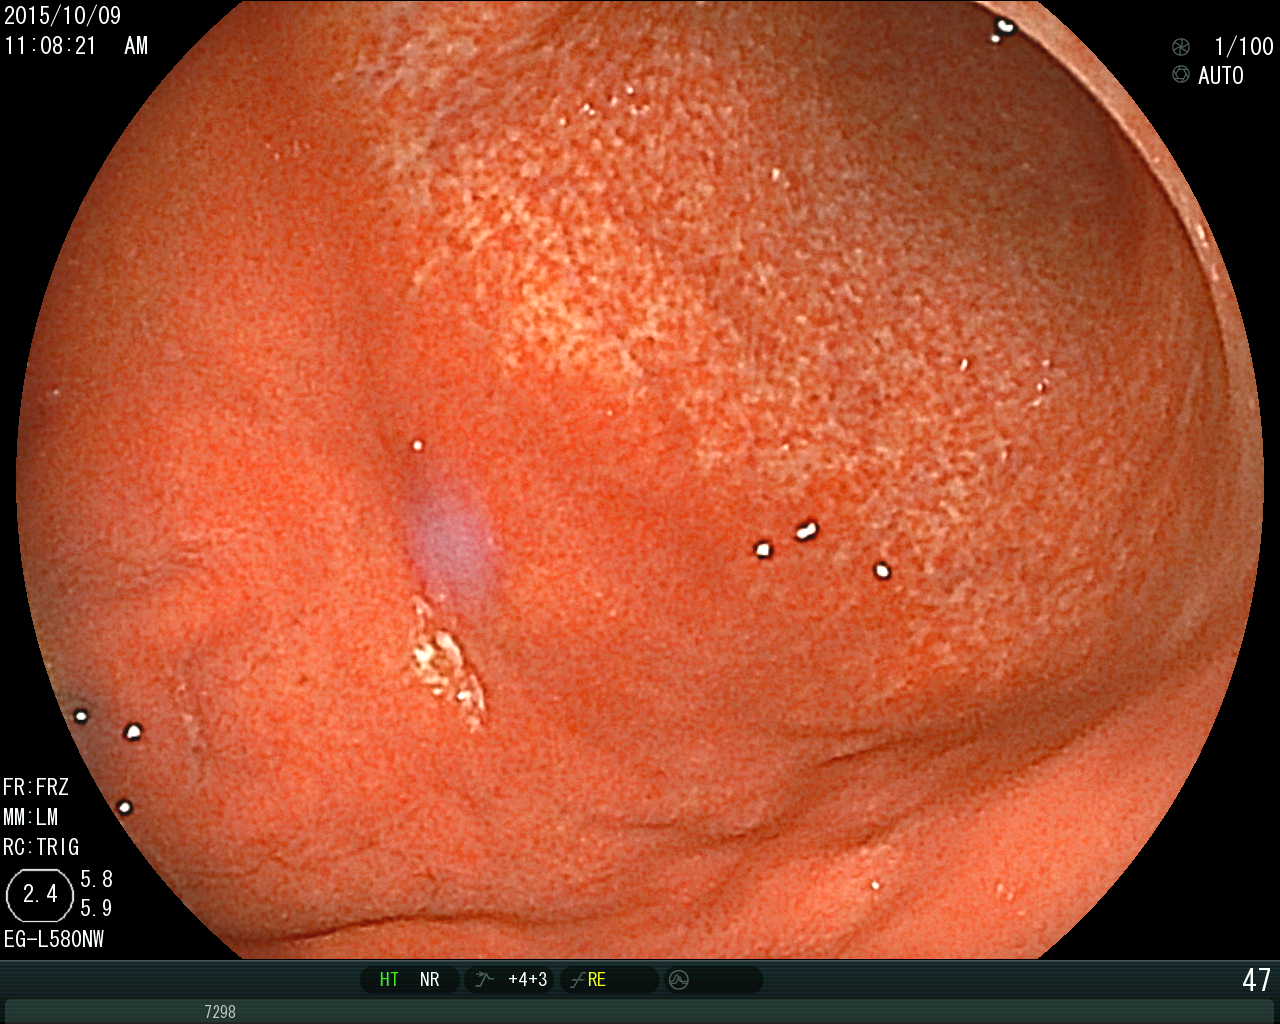

(1) 위내시경 검사

위축성 위염의 기본적인 진단은 위내시경 검사를 통해 이루어집니다. 내시경 검사 시 다음과 같은 특징적인 소견이 관찰됩니다:

- 위점막이 얇아진 상태

- 점막의 창백함

- 점막의 반짝거림

- 점막 아래 혈관이 투명하게 보임

- 위 주름의 감소